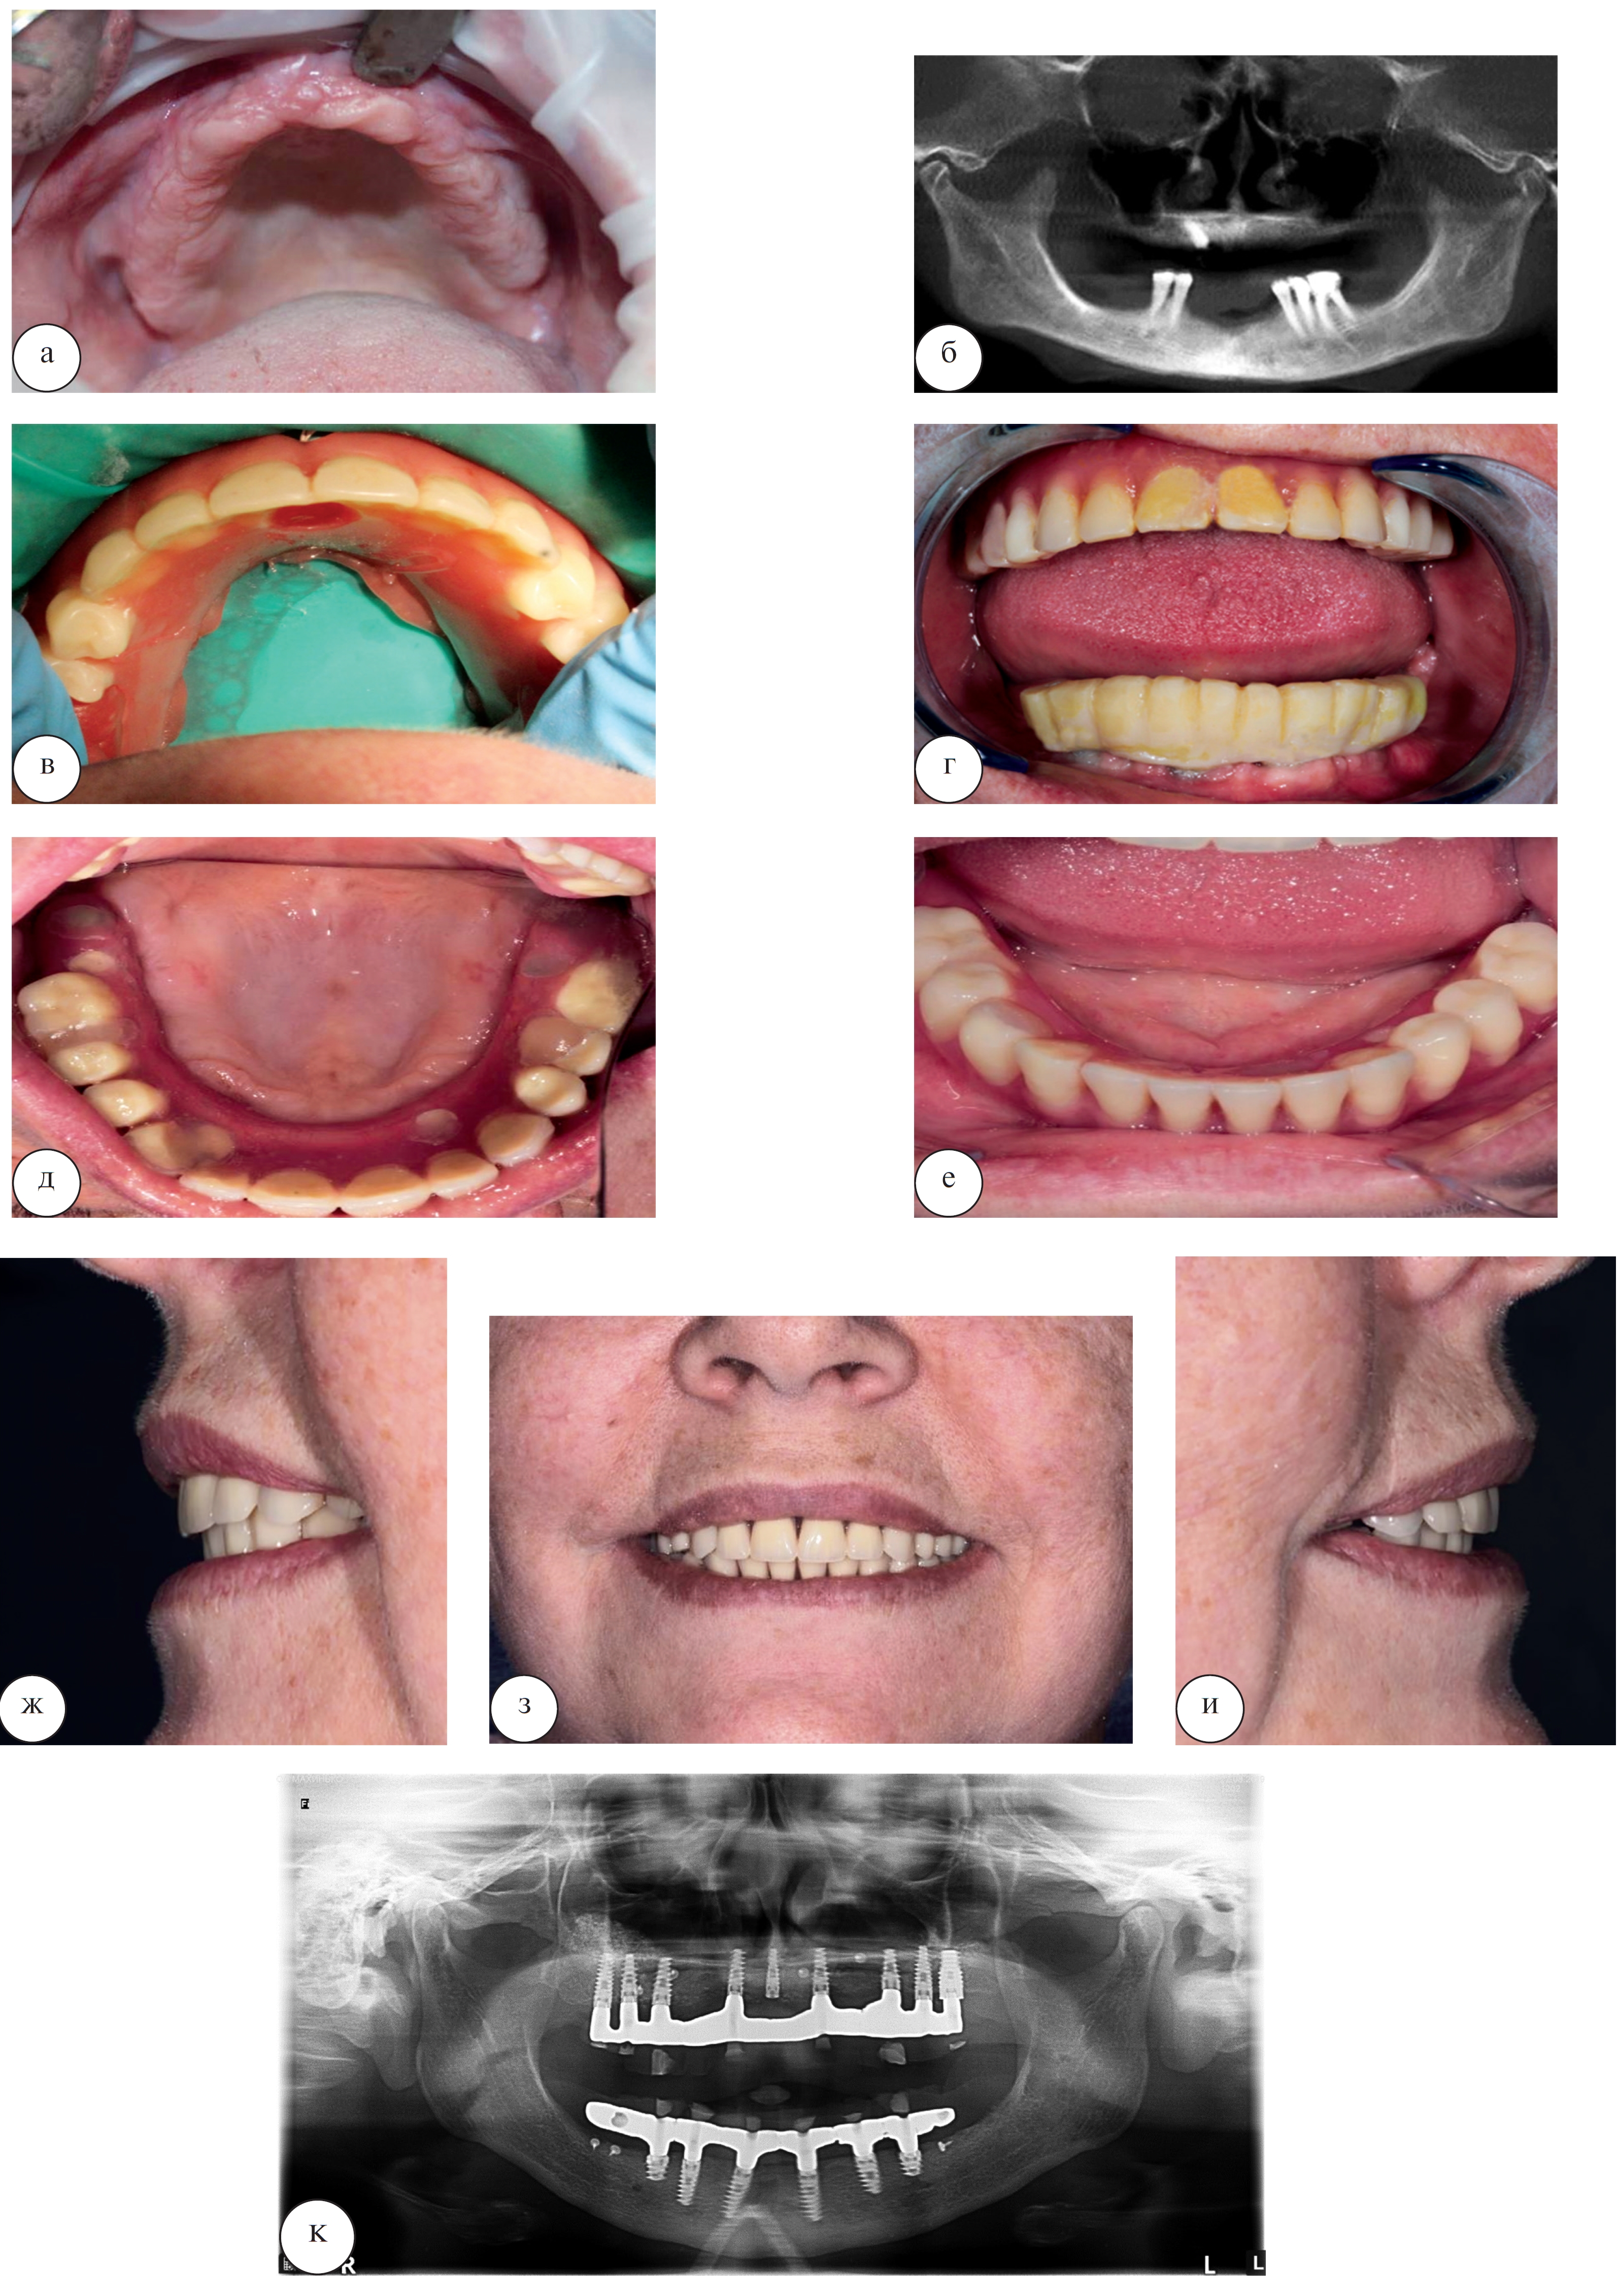

Клиническое наблюдение пациентки М. 63 лет, в котором использовалась эта методика стоматологической реабилитации, представлена на рисунке 7.

Рис. 7. Восстановление зубного ряда верхней челюсти с помощью несъемной ортопедической конструкции пациентки М. 63 лет: а – исходная клиническая картина в полости рта; б – временная ортопедическая конструкция, изготовленная методом «силиконового ключа» в день операции; в – клиническая картина в полости рта после фиксации постоянных абатментов; г – внешний вид окончательной конструкции из металлокерамики в полости рта; д – улыбка пациентки после завершения стоматологической реабилитации

Зачастую, если зубы долгое время отсутствовали на нижней или верхней челюсти или при длительном использовании пациентом полного или частичного съемного протеза, приходится сталкиваться с невозможностью проведения дентальной имплантации без увеличения объема костных и мягких тканей. Современное развитие стоматологии в целом и дентальной имплантологии в частности позволяет, даже несмотря на проведение костной пластики, в большинстве случаев выполнить реабилитацию пациента за 1 день. На рисунке 8 представлен клинический пример проведения дентальной имплантации с увеличением объема костной ткани в области альвеолярных бухт верхней челюсти пациента Г., 69 лет.

Рис. 8. Этапы стоматологической реабилитации с использованием дентальных имплантатов и проведением костной пластики на верхней челюсти и дентальной имплантации без костной пластики на нижней челюсти пациента Г. 69 лет: а – исходная клиническая картина в полости рта; б – срез компьютерной томограммы до начала лечения; в – установка временного условно-съемного акрилового протеза на верхней челюсти; г – улыбка пациента с временными акриловыми протезами на верхней и нижней челюсти; д – условно-съемные металлокерамические протезы обеих челюстей на винтовой фиксации; е – фиксация реставраций в полости рта, завершение стоматологической реабилитации

В данном случае выраженная атрофия альвеолярного отростка в дистальных отделах верхней челюсти не позволяла выполнить дентальную имплантацию без увеличения объема костной ткани по вертикали (субантральной аугментации справа и слева). На нижней челюсти стоматологическая реабилитация проводилась по стандартному протоколу без костной пластики одновременно с верхней челюстью.